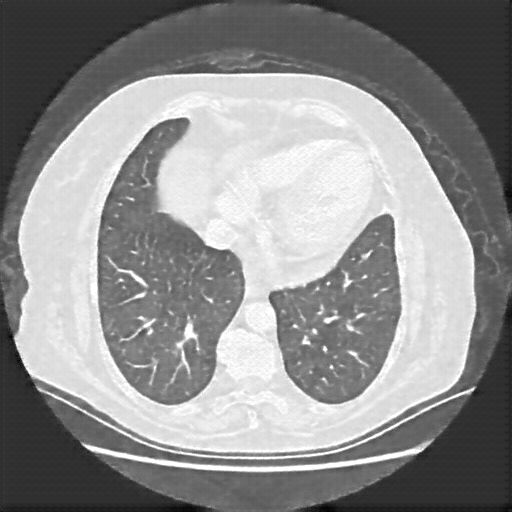

Generated VENOUS CT scan (A→B translation)

Full window (WL 1023.5, WW 4095 β†’ Low βˆ’1024, High +3071)

Lung window (WL -600, WW 1500 β†’ Low βˆ’1350, High +150)